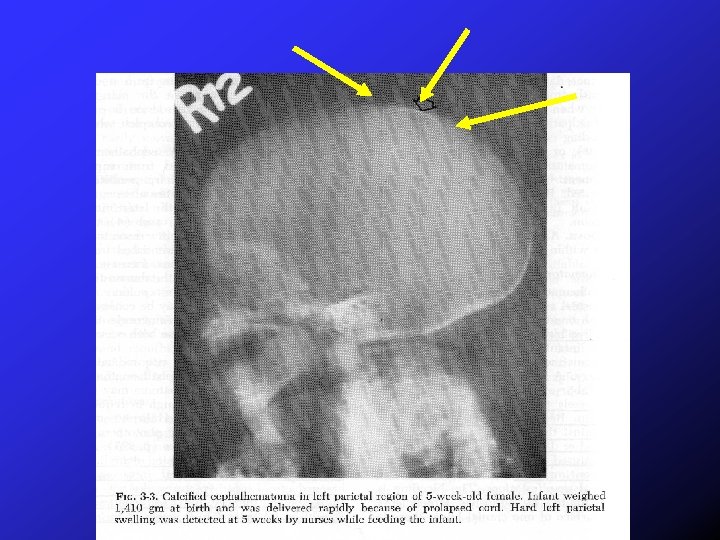

Back Front

Cephalohematoma Resolution: 2 -8 weeks with a “crater like ridge” noted as it resolves Complications: Hyperbilirubinemia, anemia, infection, calcification, osteomyelitis, skull fracture (5 % occurrence with unilateral and 18% with bilateral cephalohematoma – rarely associated morbidity) Treatment: “Expectant”